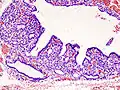

Hyperthyroidism is one of the most common endocrine conditions affecting older domesticated housecats. In the United States, up to 10% of cats over ten years old have hyperthyroidism.[45] The disease has become significantly more common since the first reports of feline hyperthyroidism in the 1970s. The most common cause of hyperthyroidism in cats is the presence of benign tumors called adenomas. 98% of cases are caused by the presence of an adenoma,[46] but the reason these cats develop such tumors continues to be studied.

The most common presenting symptoms are: rapid weight loss, tachycardia (rapid heart rate), vomiting, diarrhea, increased consumption of fluids (polydipsia), polyphasia, and increased urine production (polyuria). Other symptoms include hyperactivity, possible aggression, an unkempt appearance, and large, thick claws. Heart murmurs and a gallop rhythm can develop due to secondary hypertrophic cardiomyopathy. About 70% of afflicted cats also have enlarged thyroid glands (goiter). 10% of cats exhibit "apathetic hyperthyroidism", which is characterized by anorexia and lethargy.[47]